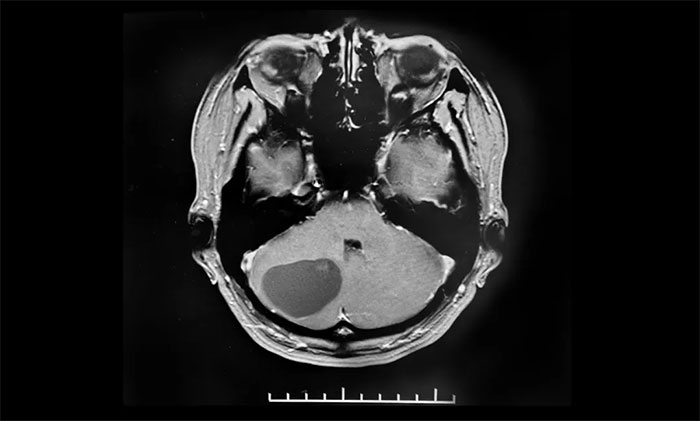

近日,上海藍十字腦科醫(yī)院6B神經(jīng)外二科就收治了一位血管母細胞瘤患者。患者為中年女性,于入院前兩個月無明顯誘因出現(xiàn)頭痛頭暈癥狀,當時未引起重視,未治療。隨著時間推移,入院前一個月,頭痛頭暈癥狀加重才就醫(yī),最終確診血管母細胞瘤。后輾轉(zhuǎn)轉(zhuǎn)入上海藍十字腦科醫(yī)院,最終經(jīng)李士其教授手術(shù),順利切除腫瘤。

▲ 右側(cè)小腦血管母細胞瘤,大小約34x34mm